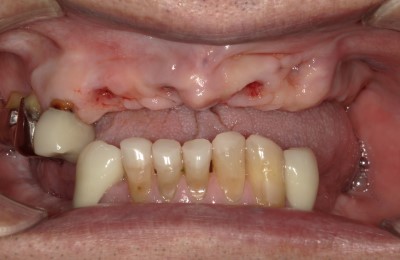

CASE01インプラント

Before

After

| 主訴 | 入れ歯以外の方法でしっかり咬みたい。 |

|---|---|

| 治療方法 | インプラントを6本埋入し、その上部をセラミックで作りしっかり咬めるようにした。 |

| 治療期間 | 約5カ月 |

| リスク | メンテナンスをしないことによるインプラント周囲炎、上部セラミックの破折。 |

| 費用 | 3,476,000円(税込) |